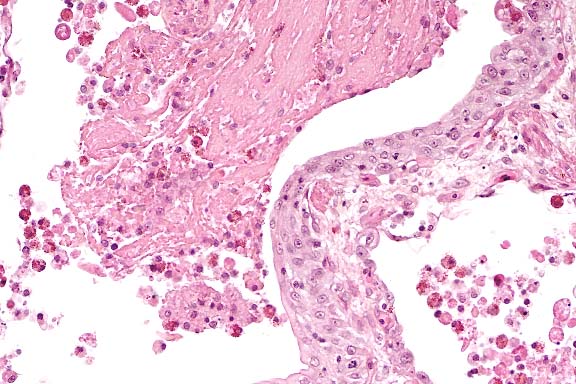

Case 28-1. Skeletal muscle. Packets of numerous pale to basophilic intrasarcoplasmal protozoa

(Microsporidia) separate viable muscle fibers. Scattered lymphocytes, heterophils, and histiocytes expand the interstitium.

40X

Contributor's Diagnosis and Comments: Skeletal muscle; myositis, acute to chronic, multifocal, moderate, with protozoa. Etiology: microsporidia

This tortoise had multifocal myofiber degeneration and necrosis accompanied by inflammation which affected skeletal muscles throughout the body. These lesions varied from acute to chronic and were associated with the presence of numerous oval 1-1.5 X 2.5-3 mm organisms located within sarcoplasm and extracellularly. These organisms could also occasionally be found within non-degenerate myofibers near the inflammatory foci. The organisms were gram positive, acid-fast, and contained single PAS-positive polar granules. The morphology and staining characteristics are typical of microsporidian protozoa.